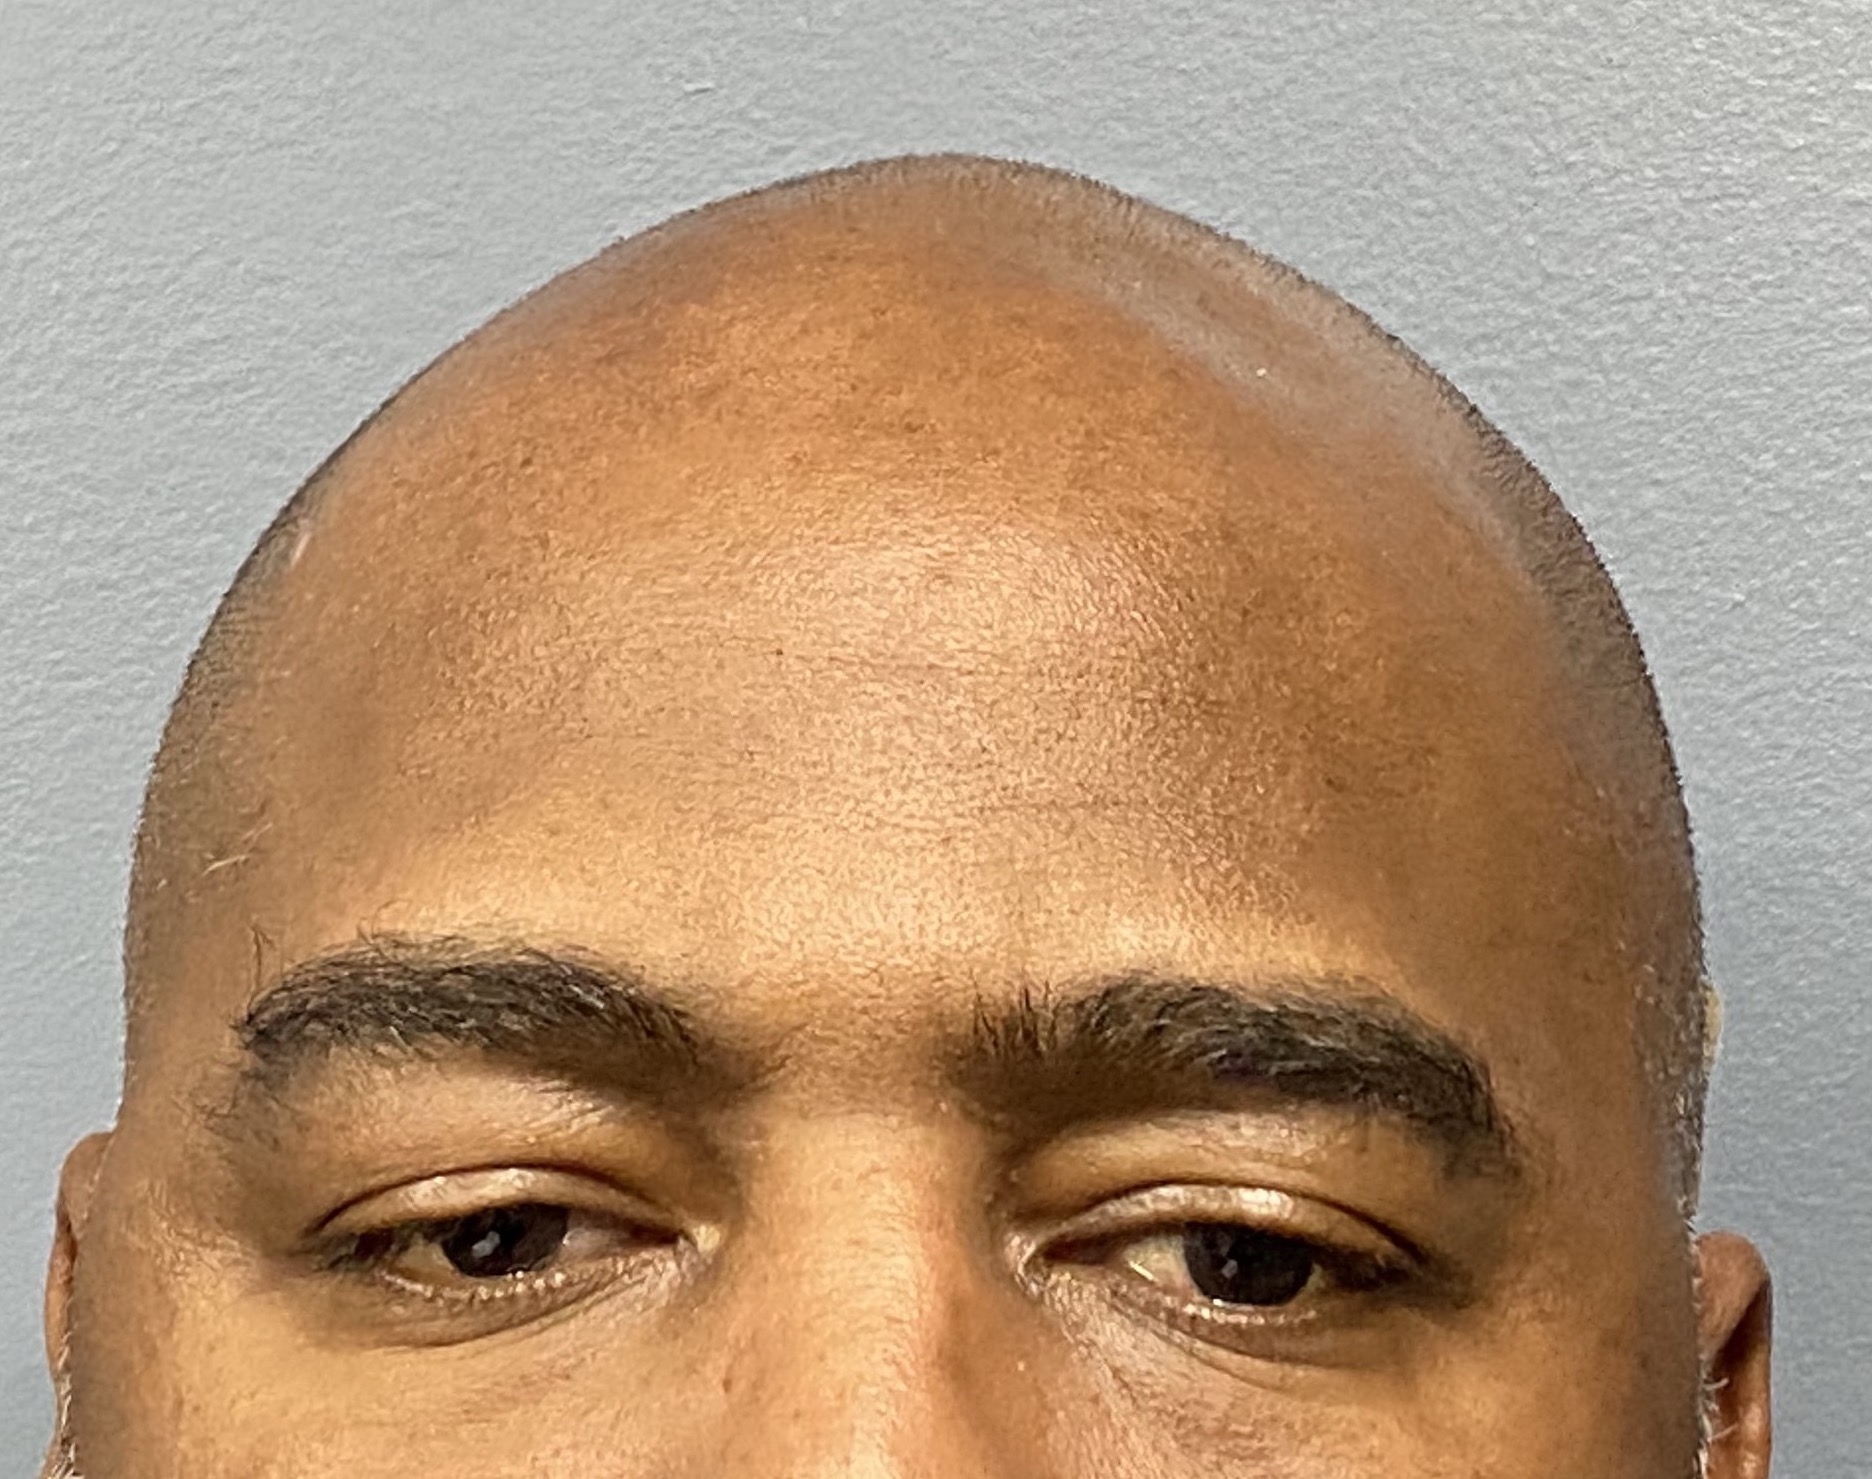

Patient 100

Desire for reshaping of an asymmetric flat back of the head in a shaved head male.

A combined back of the head reshaping procedure was done with a custom skull implant, sagittal ridge reduction and a right temporal muscle reduction.